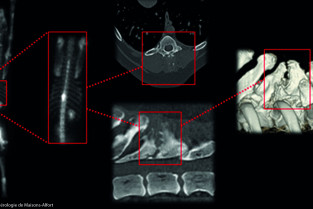

Cette journée sera consacrée cette année à l’imagerie au service de la cancérologie au quotidien. Aller au plus vite au diagnostic en présence d’une tumeur, réaliser un bilan d’extension, pouvoir donner des éléments pronostiques sont des défis que nous avons à relever tous les jours. Un programme concocté par Pauline de Fornel, Jean Laurent Thibaut et Claire Beaudu Lange pour vous aider à améliorer la prise en charge de nos patients en cancérologie.

- Determiner les indications d'un bilan d'extension au moyen de techniques d'imagerie innovantes (Echographie de contraste, IRM, Scintigraphie)